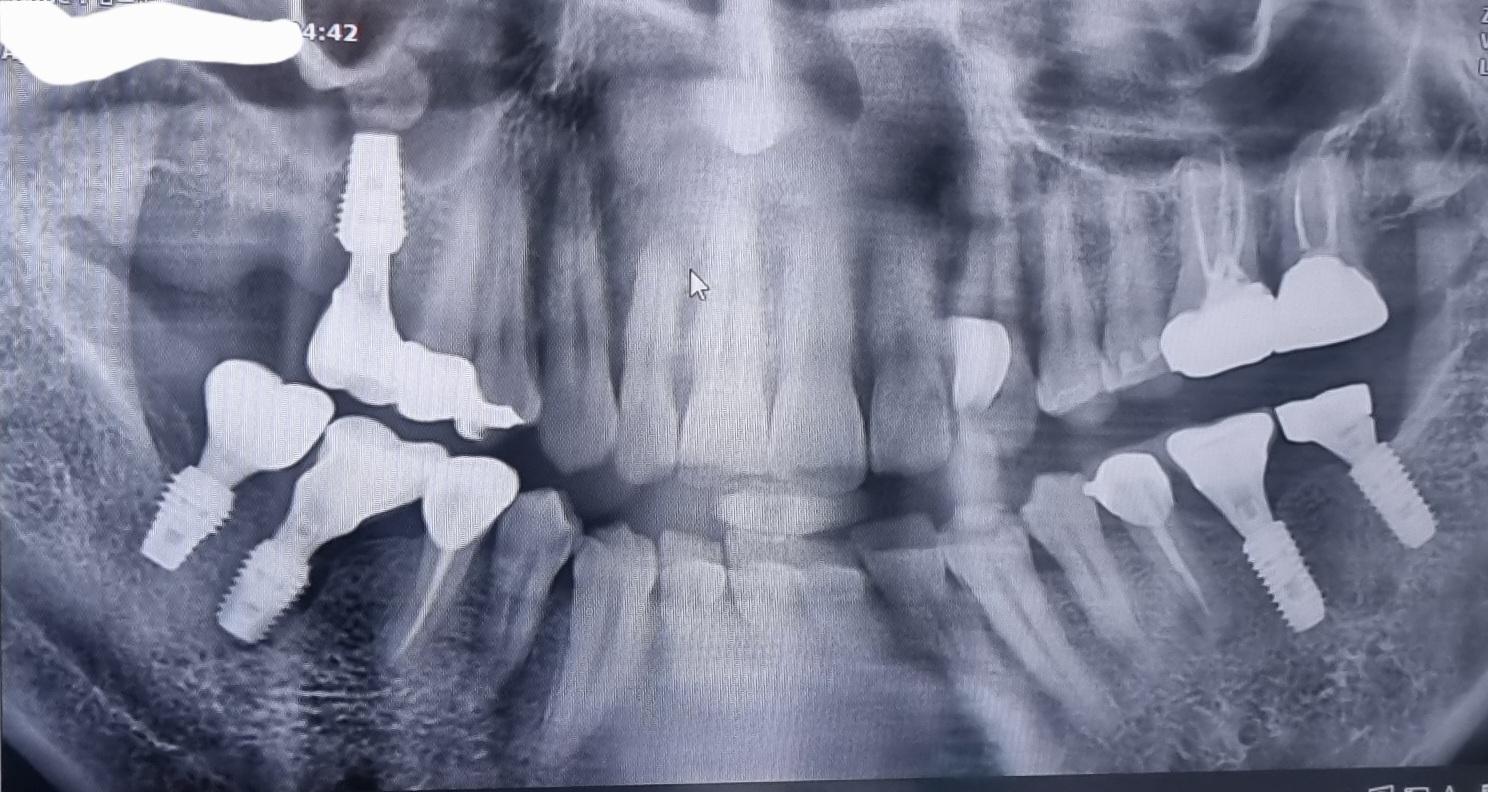

보철물 통증 지속 관련 질문 (엑스레이 첨부)

우측 하악에 임플란트 염증으로 녹은 상태에서

재식립 해서 잇몸이 안 차오른건은 인지 하고

치과의사도 과실 인정 한 상태

우측 상악에 임플란트와 인레이 부분 지속적인

통증 엑스레이 상으로 봐서는 이상이 없어

보인다고 하는데 통증이 지속되는 이유

상악동 수술 여부와 뼈이식 여부

의사는 상악동은 하였으나 뼈이식은 하지

않았다고 했습니다 임플란트 위에 상악동에 있는

석회? 돌 같은 것 임플란트 시술 전부터 있었는데

이게 통증의 원인 일수도 있는지 그렇다면

시술 전에는 브릿지 상태 가운데로 비어있었는데

통증이 있어야 하는게 아닌지 궁금하구요

좌측 상악 어금니 크라운 두곳 사이에 냄새와

통증이 있어서 재신경 치료 소견이 있는데

엑스레이 상으로는 염증이나 이런게 안 잡히는지요

좌측 하악 임플란트와 앞에 크라운이 염증으로

통증이 있어서 잇몸치료를 요구 하였으나

크라운 교체를 하자고 해서

교체를 했는데 얼마 지나지 않아 피나고 염증 발생

재 크라운 대신 잇몸치료로 해결이 가능 할지요

상악동 석회화로 인해서 통증이 생기거나 시리진 않을꺼에요. 잇몸이나 다른 치아 문제일 가능성이 높습니다. 사진상으로 좌측 하악 임플란트 주변으로 잇몸뼈가 소실된 양상이 보입니다 . 잇몸치료를 받으시면서 관리를 하시는게 좋을것같습니다.

• 안녕하세요. 천우선 치과 전문의입니다.파노라마 사진 해상도가 떨어져서 일단 보이는 대로만 설명드립니다

1. 우측 상악 1대구치 임플란트 상부 석회 돌 같은거는 보통 통증을 일으키지 않습니다 해당 부위는 중간부위 뼈손실이 의심되나 통증의 양상이 잇몸이 아프고 부으면 해당 임플란트 문제이나 이가 시리다는 느낌이 든다면 임플란트 앞에 치아들이 원인이어서 상악우측2소구치 또는 상악우측1소구치 신경치료가 필요 할 수 있습니다 아마 임플란트 말고 앞에 치아들이 문제여서 계속 통증이 생기는 듯 한 의심이 듭니다

2.우측 하악 1대구치 임플란트는 여기도 중간부위 뼈손실이 의심되나 경과 관찰 후 불편시 재식립하시거나 지켜보거나 해야 할거 같습니다

3.좌측 상악 어금니 크라운 두곳 사이에 냄새는 두 크라운 사이에 음식물이 껴서 잇몸이 부으면 구취와 통증이 생길수 있습니다 엑스레이상 신경치료는 문제 없어 보입니다

4.좌측 하악 임플란트와 앞에 크라운이 염증으로 통증이 있다고 하셨는데 임플란트는 문제 없고 그 앞에 신경치료 한 치아 뿌리 쪽 염증이 의심되어 크라운 치료가 아닌 재신경치료가 필요할수 있습니다

통증으로 불편시 대학병원(보존과) 가보시는 거 권유드립니다